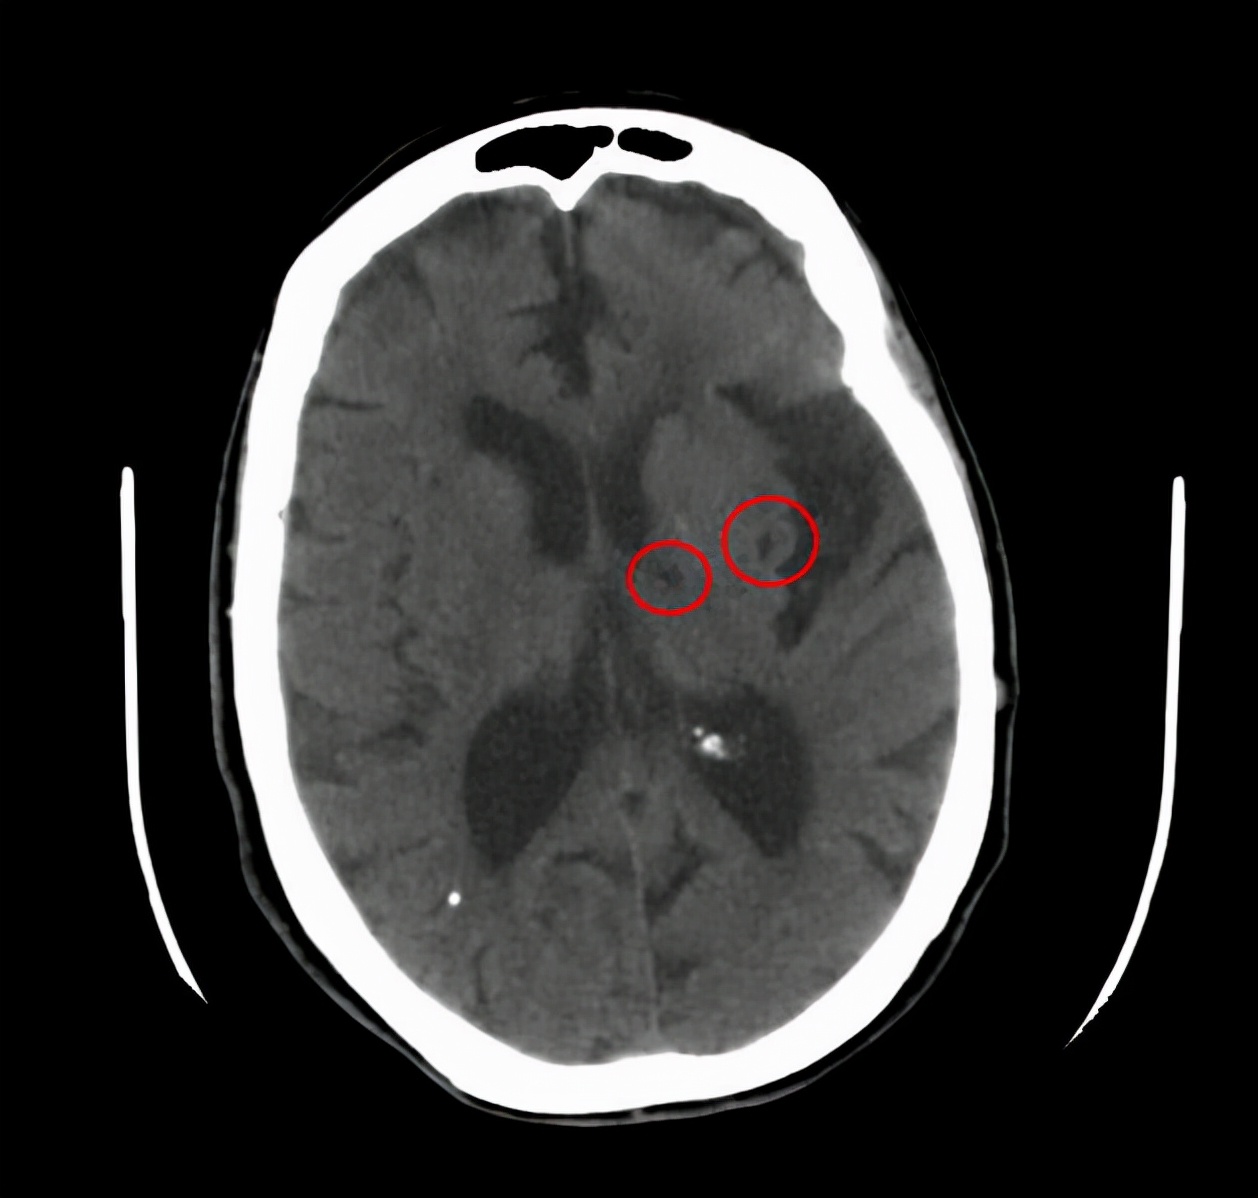

二、无症状的腔梗。

如果出现腔隙性脑梗死该怎么办呢?

但是如果没什么表现,仅仅是在体检或者在检查其他疾病的过程中发现有腔梗,这个时候该怎么办呢?

临床当中这种情况是很常见的,我们称为无症状的腔隙性脑梗死,对于这类患者,请您别害怕。

虽然我们称之为脑梗死,但他对我们的危害并不大,只需要改善生活方式,积极预防下一次腔梗就可以了。

需要用药吗?需要用治疗脑梗死的扩血管药物吗?是不是应该活血化瘀呢?

都不用,千万别被骗。